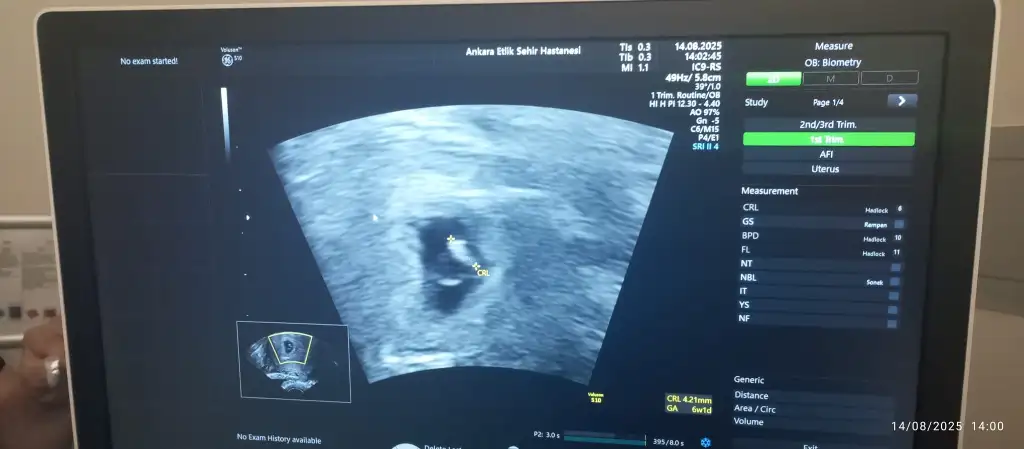

Ben 5+2de keseyi, 7+0da da kalp atışını ve bebeği gördüm:) amin inşallahKızlar keseyi ve kalbi kaçıncı haftalarda gördünüzzhepimiz sağlıkla yavrularımızı kucağımıza alalım inşallah

Canım ben şimdi dr dan çıktım 5+2 tek kese dediHadi hayırlısı olsun canımmmm güzel haberlerini bekliyorum

Yaaa hayirli uğurlu olsun ama bazen 6. haftadan sonra tek yumurta ikiz olayı var ise gözükebilirmis. Zaten suan embriyo oluşumun yeni başladı. Biraz daha bekleyelim bakalımCanım ben şimdi dr dan çıktım 5+2 tek kese dedi